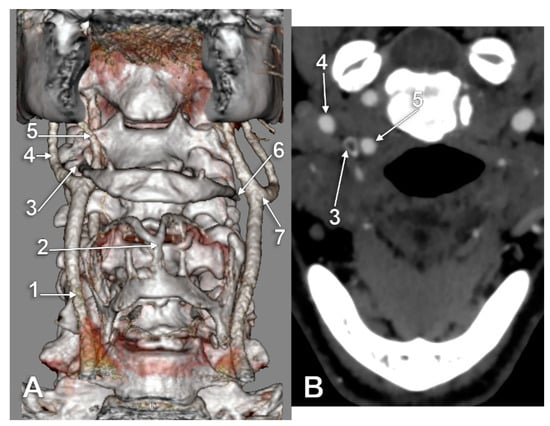

The Carotid–Hyoid Topography Is Variable

3. Results